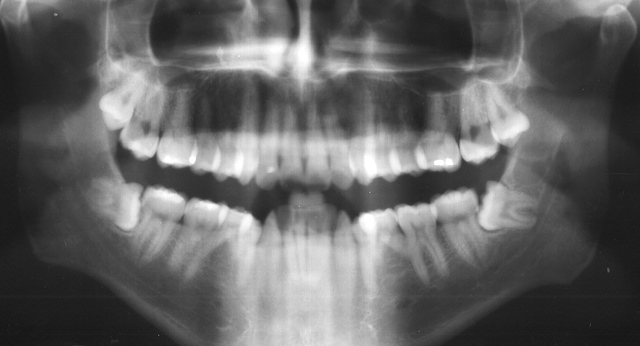

Existem quatro dentes do siso: dois superiores, direito e esquerdo, e dois inferiores, também direito e esquerdo. O nome mais apropriado para os dentes do siso é 3ºmolar. Podem existir, raramente, até 4ºs molares!